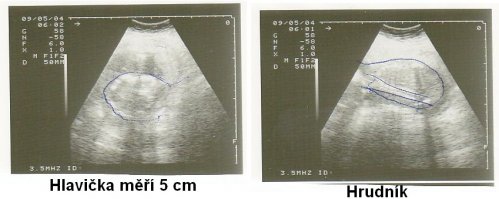

so.19.9.2009 40tt narodil se nám chlapeček Honzík v 11:25 hod. vážil 3900 g a měřil 53 cm